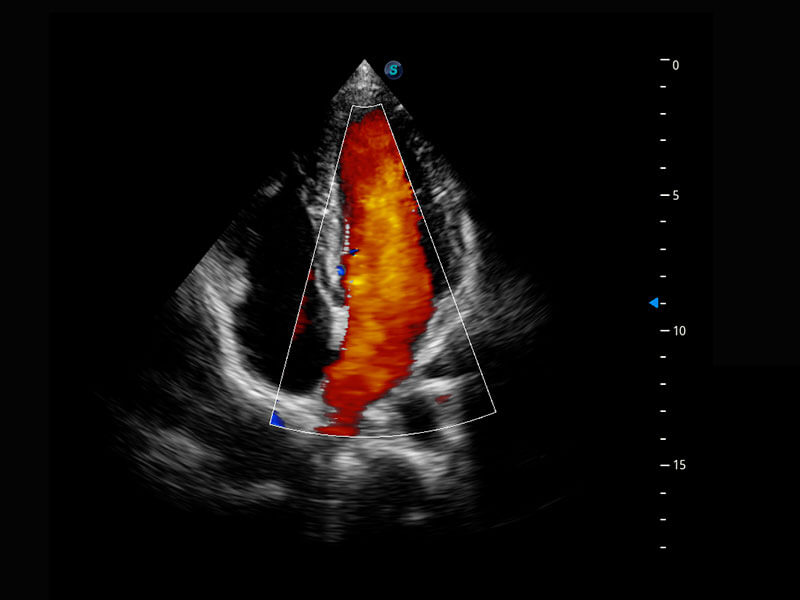

胎心筛查

P60搭载一系列胎儿心脏成像技术,实现精细的胎儿心脏评估。

• 四腔切面

• 四腔心血流

• 右室双出口

• 胎心容积成像